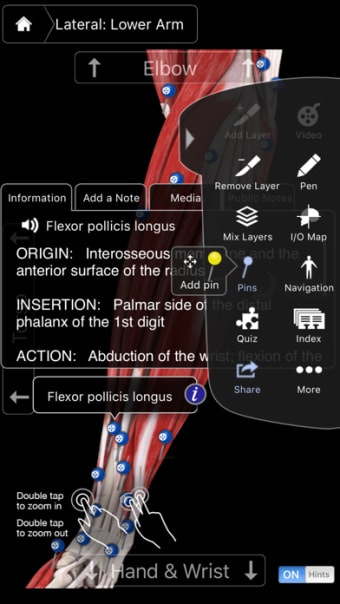

Muscle System Pro III - IPhoneเป็นโปรแกรมเวอร์ชันเต็มสำหรับ iPhone ซึ่งอยู่ในหมวดหมู่ 'ยา'

เกี่ยวกับ Muscle System Pro III - IPhone สำหรับ iPhone

Muscle System Pro III - IPhone พร้อมใช้งานสำหรับ iOS 12.1.2 ขึ้นไป เวอร์ชันปัจจุบันของโปรแกรมคือ 3.8.2 และคุณสามารถเรียกใช้ได้ในภาษาอังกฤษเท่านั้น